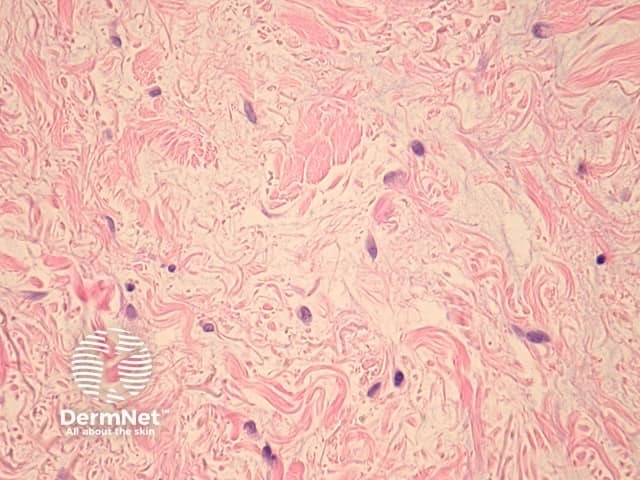

In DLE, sections reveal the dermis contains a perivascular and periadnexal lymphohistiocytic infiltrate under an interface dermatitis (figure 1). The epidermal interface activity shows degeneration of the basal layer, apoptotic keratinocytes and a marked thickening of the basement membrane (figures 2, 3). In well-established lesions, there may be marked follicular plugging (figure 4) and sometimes an epidermal reaction which may mimic a squamous cell carcinoma (verrucous lupus erythematosus). There is a characteristic lymphohistiocytic infiltrate surrounding appendages and vessels (figure 5). Deposition of dermal mucin may be impressive (figure 6).

Figure 6

Thickening of the basement membrane may be highlighted with periodic acid-Schiff (PAS). Mucin may be highlighted with alcian blue stain or colloidal iron.